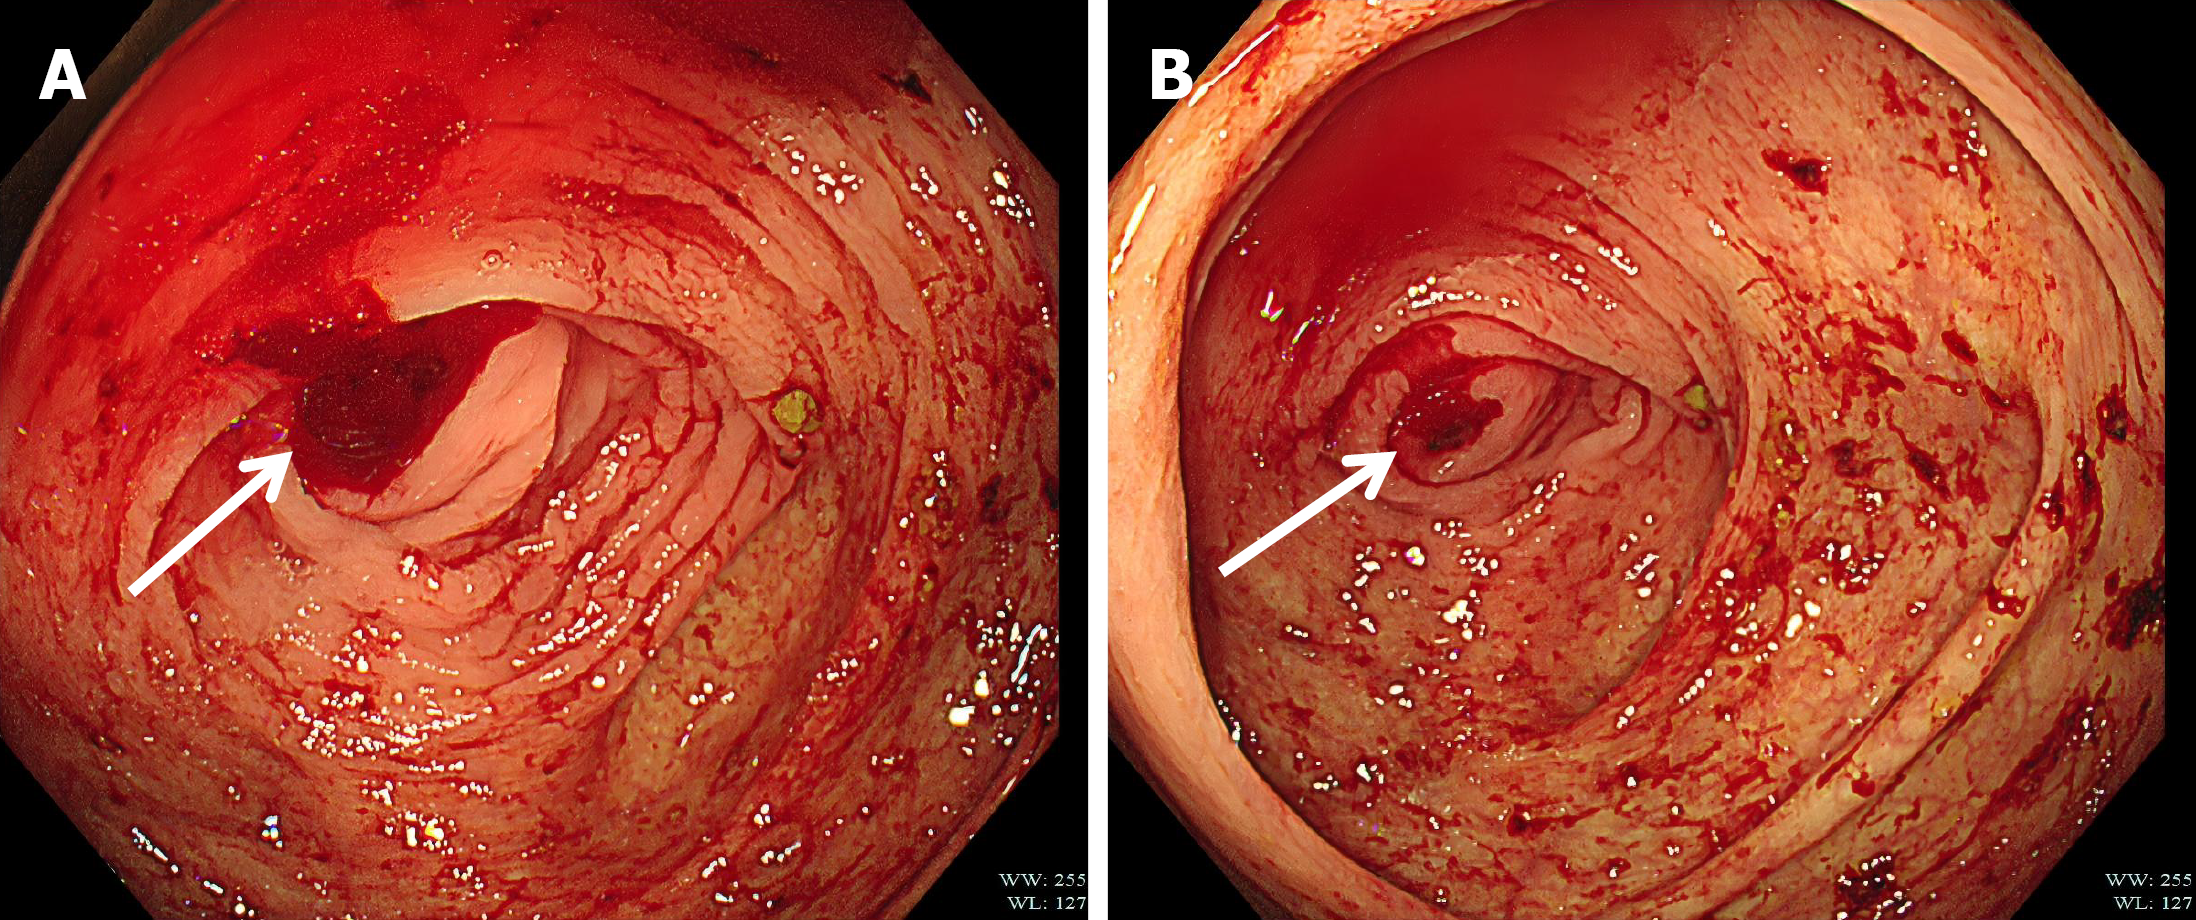

The preoperative routine blood test showed that the hemoglobin level was 114 g/L. The patient underwent an emergency laparoscopic appendectomy. Intraoperatively, the resected appendix measured 5 cm and showed no evidence of gangrene or perforation. There was no blood, fluid or pus in the pelvic cavity. Postoperatively, analgesic and nutritional medications were administered. Histopathological examination of the resected appendix revealed abnormal veins penetrating the muscular layers of the appendix (Figure 3).

Figure 3

Figure 3 The histopathology of the resected specimen. Abnormal veins piercing the muscle layers of the appendix can be seen. Blue arrow: Abnormal veins.